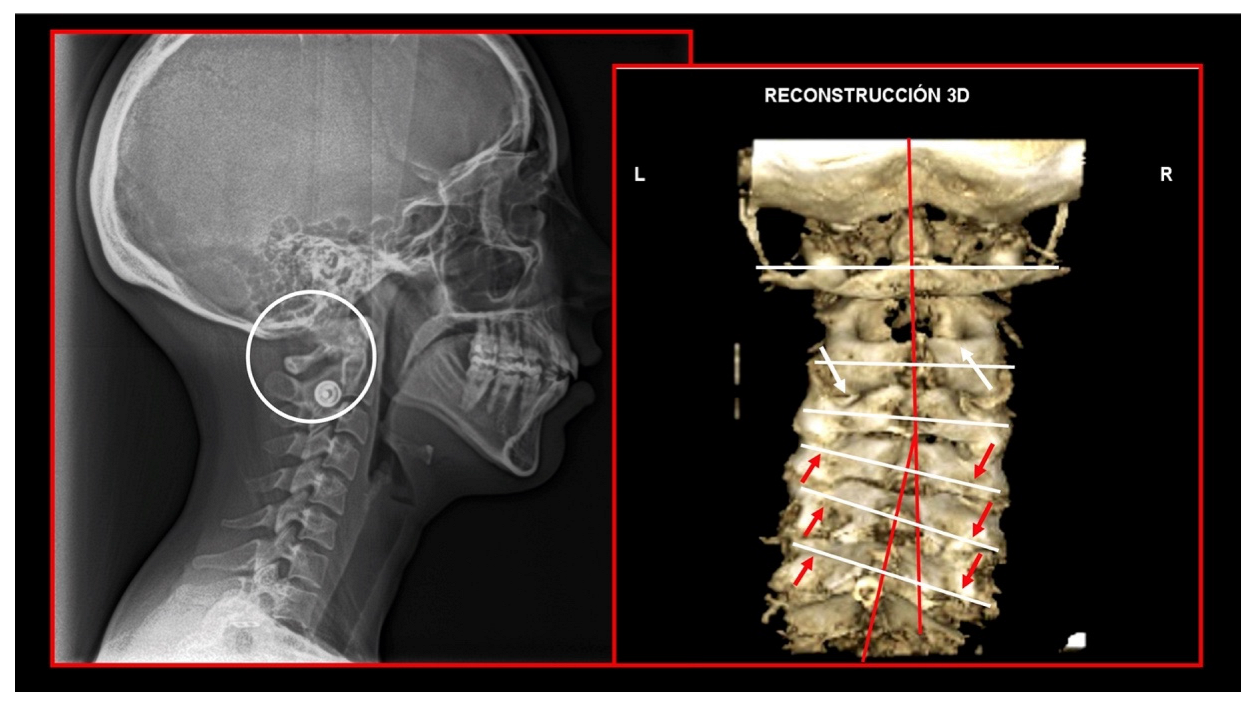

10.1. Neck X-ray

10.2. Computed Tomography of Cervical Spine

11.5. Axis and Atlas Derotation